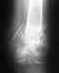

Добрый день. Оперировать не рекомендовали. После 3-х лет после операции- вот такая картина. Прокомментируйте пожалуйста снимки.